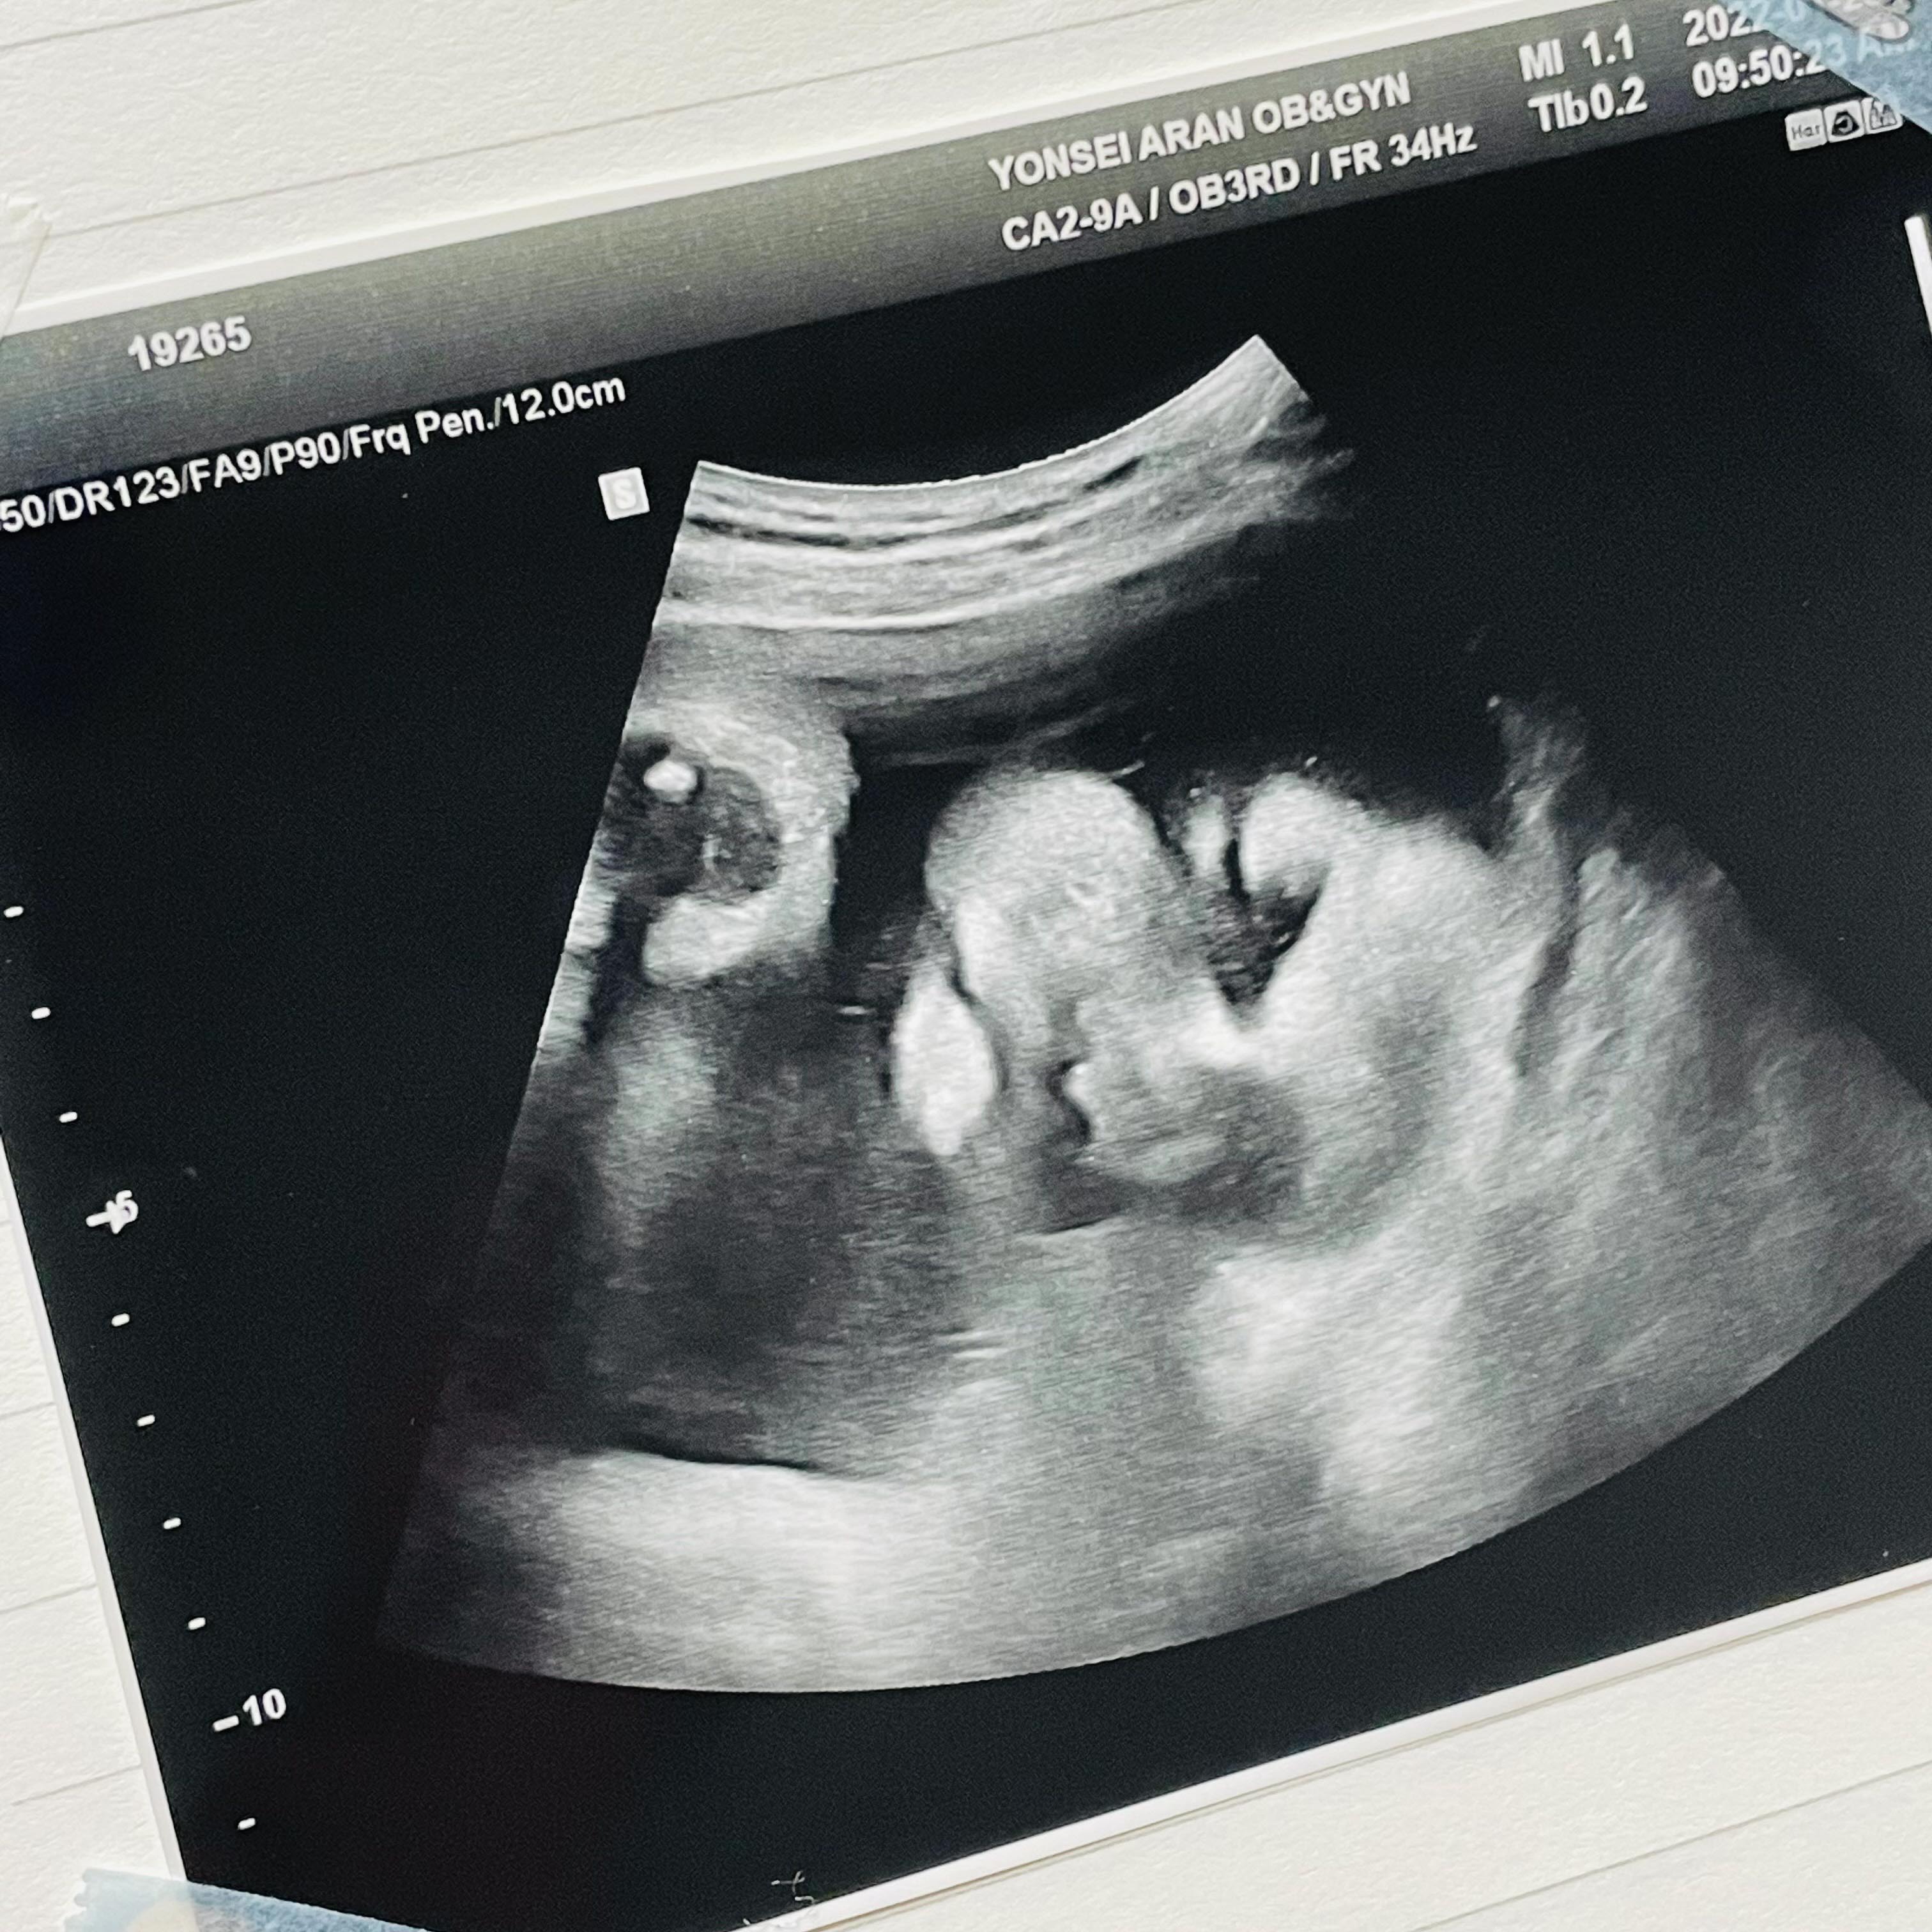

애기가 얼굴이 너무 잘보인다며 웃으셨다.

하나도 안내려왔다고...ㅠ

그와중에 머리는 역시 커졌고,